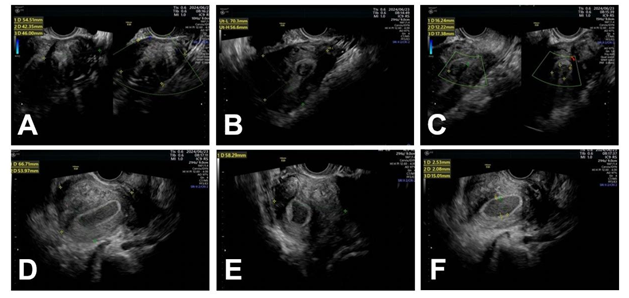

Patient, female, 45 years old, presented to

our hospital on June 23, 2024, due to "progressive dysmenorrhea for 10

years and prolonged menstrual period for 3 months." The outpatient

ultrasound suggested the possibility of a rudimentary uterine horn, a uterine

fibroid on the left side, and adenomyosis on the right side (Figure 1), leading to admission to the hospital. The